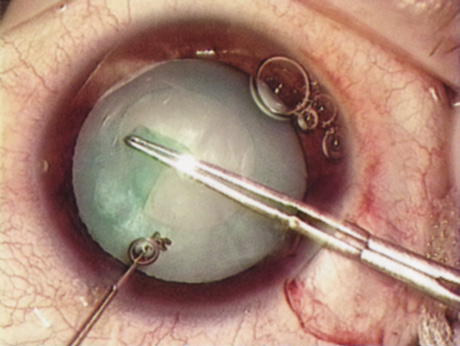

Back to Top